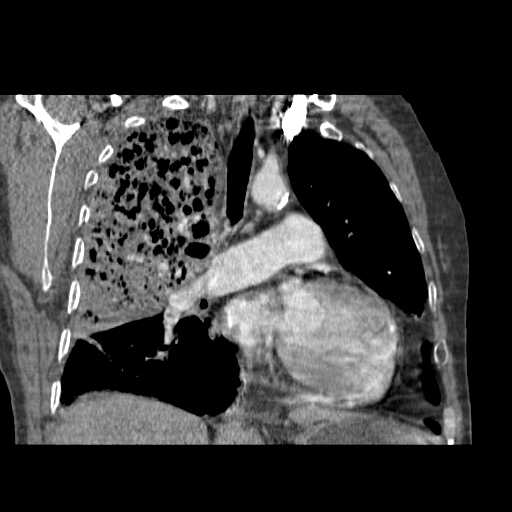

2008.8.17ct

病变从8.11-8.17明显改变,增多,以蜂窝状改变为主,类蜂窝肺,似弥漫性肺泡癌,但是病变进展太快,不符合弥漫性细支气管肺泡癌。因此考虑为特殊微生物感染,多以霉菌类常见,建议细菌微生物学检查。

疑点二:影象表现怪异,大片阴影内见多发筛孔征,如何解释.

结合临床慢支炎肺气肿,肺心病病史,三次胸片观察可见病情发展变化迅速,病情凶险,考虑多重感染伴ards.